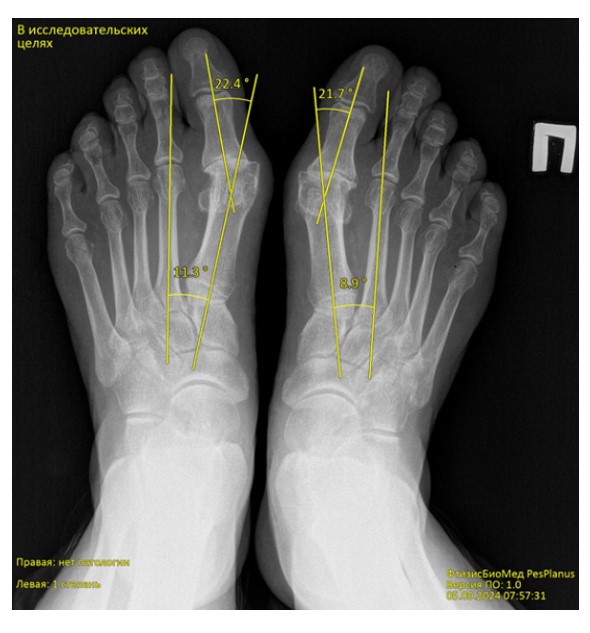

Chương trình phân tích tự động ảnh ‘X-quang bàn chân’ phát hiện bàn chân bẹt dọc và bẹt ngang

FtizisBioMed PesPlanus được phát triển nhằm phân tích tự động hình ảnh X-quang kỹ thuật số của bàn chân, hỗ trợ bác sĩ trong việc:

Phát hiện sớm các dấu hiệu bàn chân bẹt dọc và bẹt ngang;

Chuẩn hóa và nâng cao độ chính xác trong đánh giá hình ảnh X-quang;

Giải pháp công nghệ

Chương trình ứng dụng trí tuệ nhân tạo y tế (Medical AI) và các mô hình học máy tiên tiến để phân tích hình ảnh X-quang bàn chân. Hệ thống được huấn luyện trên tập dữ liệu lớn đã được gán nhãn bởi các chuyên gia đầu ngành, đảm bảo độ tin cậy và khả năng tái lập kết quả cao.

Tự động phát hiện và nhận diện nhiều dấu hiệu bệnh lý hình thái bàn chân, hỗ trợ tự động hóa bước đọc phim ban đầu.